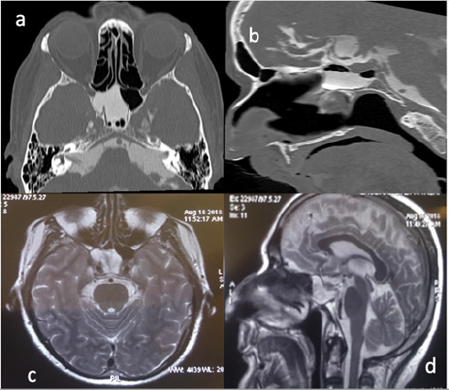

A 57-year-old man referred for clear watery discharge from the right nostril of no obvious cause. He suffered from intermittent rhinorrhea starting 6 months prior to arrival. He reported recent history of bacterial meningitis one month ago, which was treated successfully at an outside hospital. On admission, he had no focal neurological deficits. Nasal fluid tested positive for beta 2 transferrin. Brain MRI revealed that the right sphenoid sinus was filled with CSF (Figure 4). CT cisternography showed that the contrast material passed from the prepontine cistern into the sphenoid sinus through this bone defect in the clivus (Figure 4). After intrathecal administration of 0.25mL of 10% fluorescein with 10 mL of cerebrospinal fluid the patient underwent endoscopic trans nasal approach. After stripping the mucosa from posterior wall of sphenoid sinus, CSF leak was observed in the upper region of clivus just below the sella at the midline (Figure 5). The defect was closed by abdominal fat and reinforced by fasciculata and naso septal flap. At the During 30-month follow-up appointment, no signs of recurrence were found. In both above reviewed cases, a lumbar drain was not placed pre or postoperatively.

Figure 4: (a) CT cisternography showing right sphenoid sinus filled with CSF and

(b) The entry of cerebrospinal fluid into the sphenoid sinus.

(c) Axial T 2weight MRI revealed right sphenoid sinus filled with csf.

(d) Csf leakage from prepontine cistern to sphenoid sinus.